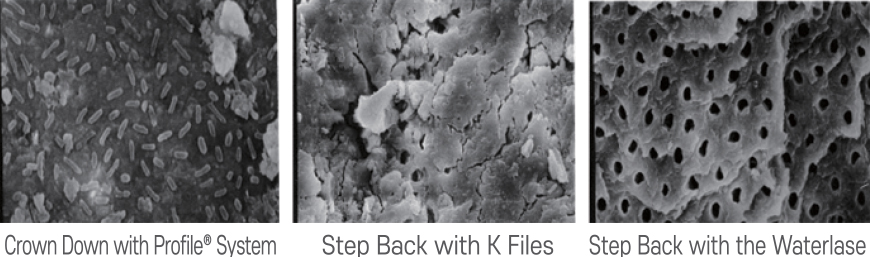

Cross-sectional Comparison under Scanning Electron Microscope (×1000 Magnification)

Conventional Filing Techniques vs. YSGG Laser

Open dentinal tubules and significant reduction of microorganisms in the canal aids in ensuring successful endodontic therapies.

- Minimal secondary infection from residual smear layer

No smear layer remains, and open dentinal tubules ensure complete bacterial removal

Surface Preparation Comparison